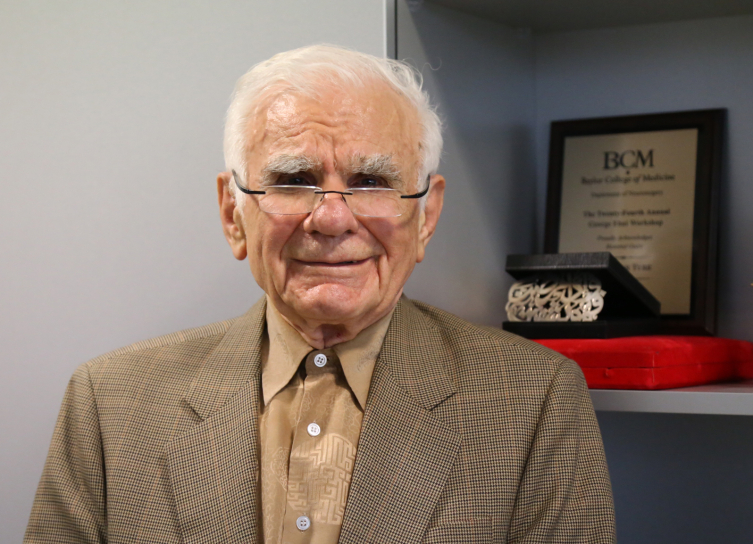

Zürich Üniversitesinden 1993’te emekli olan Yaşargil, 1994’te ABD’deki Arkansas Üniversitesi Tıp Fakültesinde profesör olarak görev yapmaya başladı. Yaşargil, burada yeni bir mikronöroşirurji laboratuvarı kurarak ameliyatlar gerçekleştirdi ve eğitimler verdi.

Yaşargil, çalışmalarıyla Arkansas Üniversitesinde kurulan “Yaşargil Kürsüsü” ve düzenlenen “Gazi ve Dianne Yaşargil Yıllık Konferansı” ile onurlandırıldı.

Prof. Yaşargil adına Oxford (İngiltere), Little Rock (ABD) ve Pekin (Çin) gibi şehirlerde mikrocerrahi laboratuvarları kuruldu.

Zürich Üniversitesi Tıp Fakültesi, Kasım 2014’te başlattığı “Yıllık Yaşargil Konferansları” ile Yaşargil’in bilimsel katkılarını onurlandırdı.